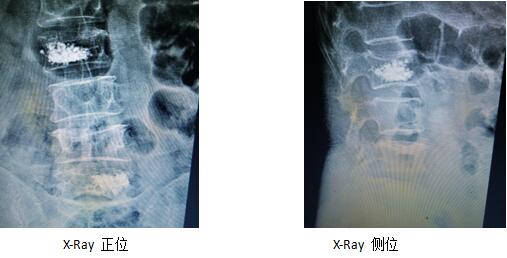

術(shù)前影像學(xué)片